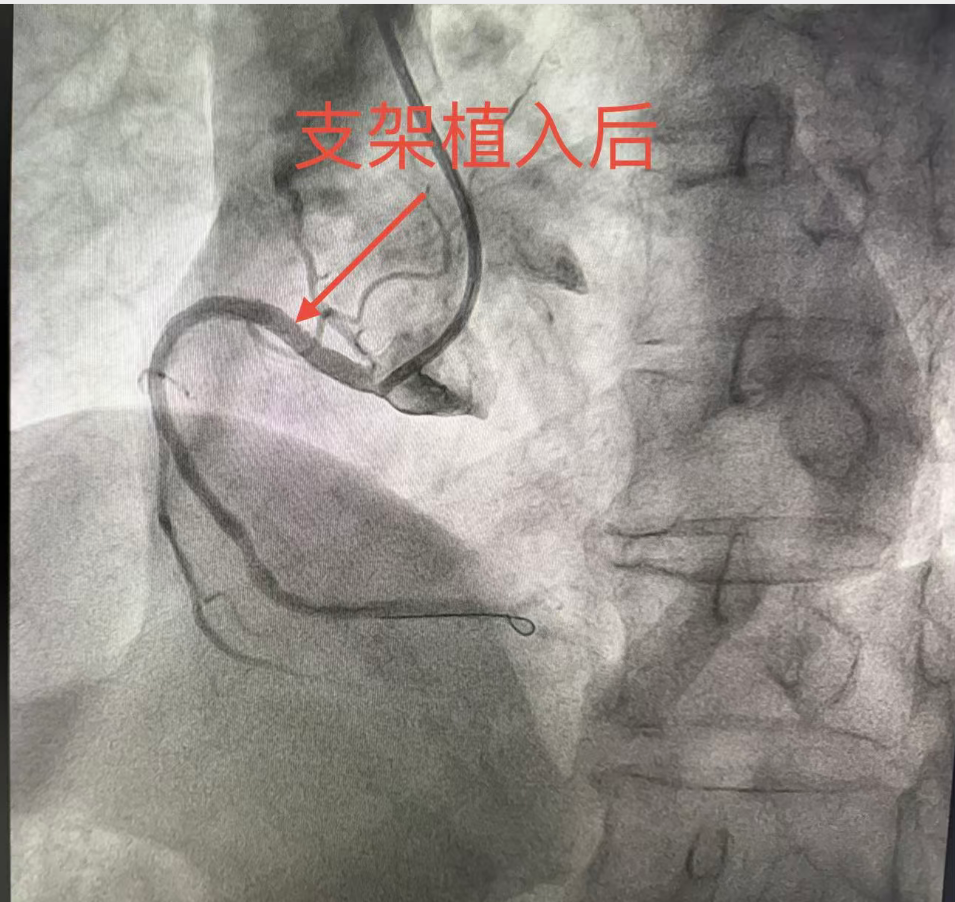

入院后,陕西冶金医院血管外科团队安排专科检查,结合症状与检查结果

结合症状与检查结果,明确诊断:1.右下肢大隐静脉曲张;2.右下肢大隐静脉瓣功能不全。

陕西冶金医院血管外科王玉德主任与党金鑫医生针对患者病情采用微创综合治疗。得益于微创术式的优势,术后李阿姨恢复速度远超预期,当天就可以下床正常活动,困扰她多年的腿部胀痛、酸胀不适感瞬间得到明显缓解,整个人的精神状态都好了很多。